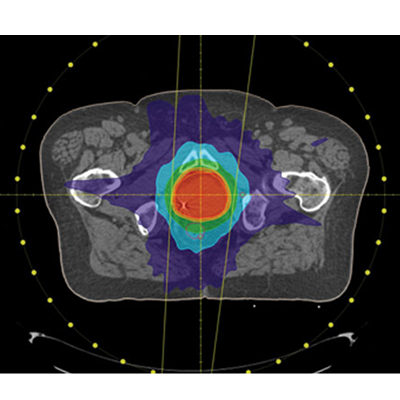

Panther TPS combines precision, automation, and flexibility to simplify treatment planning across VMAT, IMRT, 3DCRT, and Brachytherapy workflows.

Optimizes plans for machines that are capable of either variable or constant dose rate rotational delivery. Utilizing machine parameters (such as, gantry speed, collimator speed, and leaf movement), single or multiple arc plans are produced to reduce treatment delivery time and/or improve the quality of care.

Powered by Prowess’ CCCS dose calculation engine and patented Direct Aperture Optimization (DAO) algorithm; all delivery constraints are utilized within the optimization process, creating an interactive planning system that produces quality plans with minimal monitor units and segments.

Planning for photon, electron and Co-60 beams with multiple dose calculation algorithms. Plan templates are available to reduce the time needed to setup repetitive beam arrangements and beams can be shaped using various MLC fit options, block, wedges, and bolus.